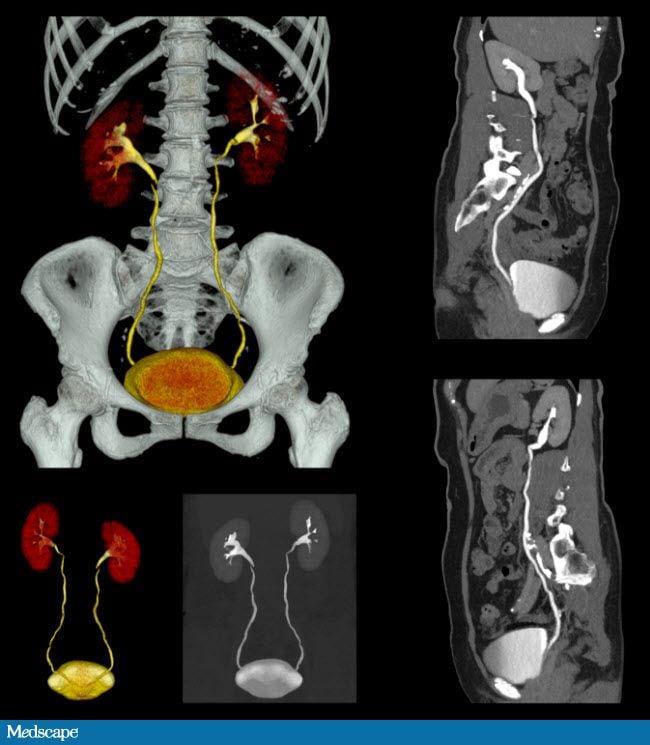

Побочки после кт

Побочки после кт 114 фотографий